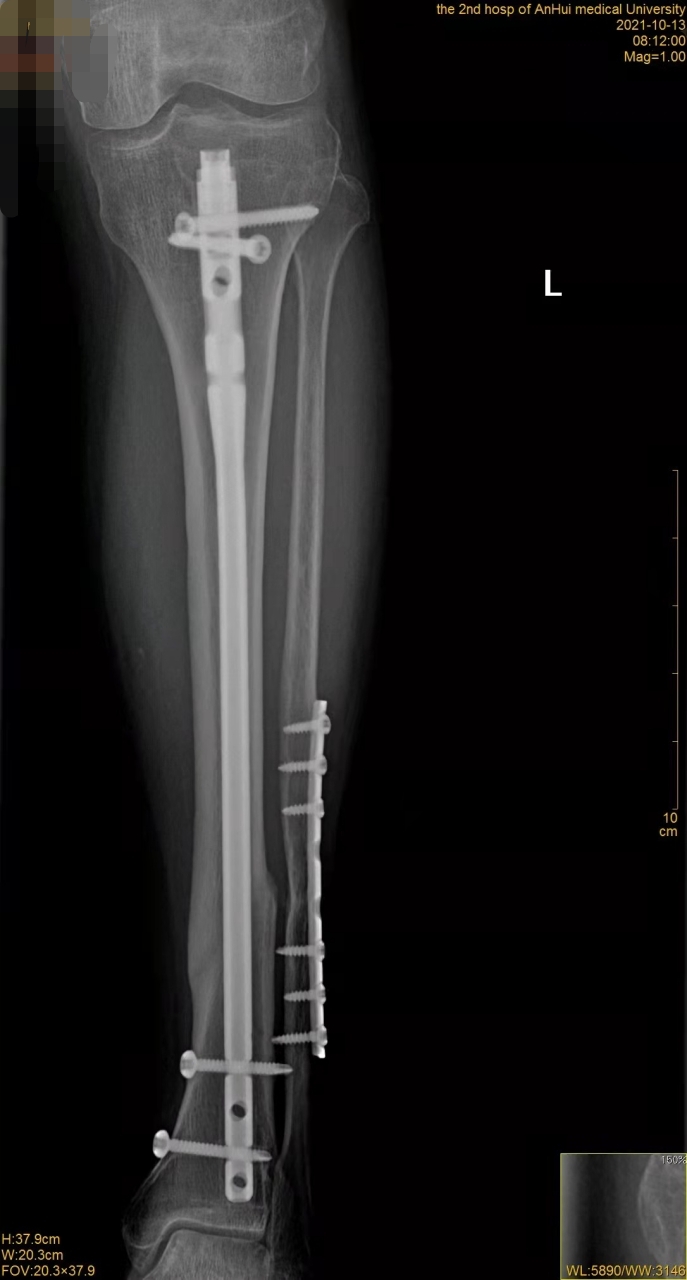

郭嫂立马被送到医院进行治疗,接受了左侧胫腓骨骨折内固定术,手术非常顺利。因为郭嫂身体底子好,再加上年龄也不算太大,术后恢复得也很好。